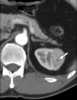

Segmental cystic disease

Caroli disease (communicating cavernous ectasia, or congenital cystic dilatation of the intrahepatic biliary tree) is a rare inherited disorder characterized by cystic dilatation (or ectasia) of the bile ducts within the liver. There are two patterns of Caroli disease: focal or simple Caroli disease consists of abnormally widened bile ducts affecting an isolated portion of liver. [Source: Wikipedia ]